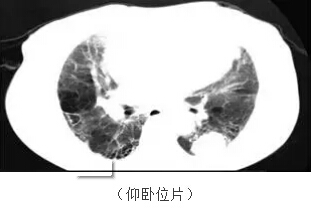

第二位患者已經(jīng)80多歲了,一直有慢性的肺心病,體檢發(fā)現(xiàn)了肺上一個(gè)3cm左右的腫塊,得知有局部消融這種微小創(chuàng)傷的治療手段,仿佛發(fā)現(xiàn)了救命稻草。

從上圖看患者肺部有嚴(yán)重的肺纖維化、肺大泡,肺功能很不好,左下肺還有一個(gè)3cm左右的腫塊